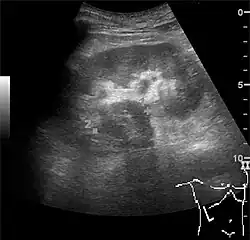

US is useful for diagnostic and prognostic purposes in chronic kidney disease. Whether the underlying pathologic change is glomerular sclerosis, tubular atrophy, interstitial fibrosis or inflammation, the result is often increased echogenicity of the cortex. The echogenicity of the kidney should be related to the echogenicity of either the liver or the spleen (Figure 22 and Figure 23). Moreover, decreased renal size and cortical thinning are also often seen and especially when disease progresses (Figure 24 and Figure 25). However, kidney size correlates to height, and short persons tend to have small kidneys; thus, kidney size as the only parameter is not reliable.[1]

Figure 22. Chronic renal disease caused by glomerulonephritis with increased echogenicity and reduced cortical thickness. Measurement of kidney length on the US image is illustrated by '+' and a dashed line.[1] -

Figure 23. Nephrotic syndrome. Hyperechoic kidney without demarcation of cortex and medulla.[1] -